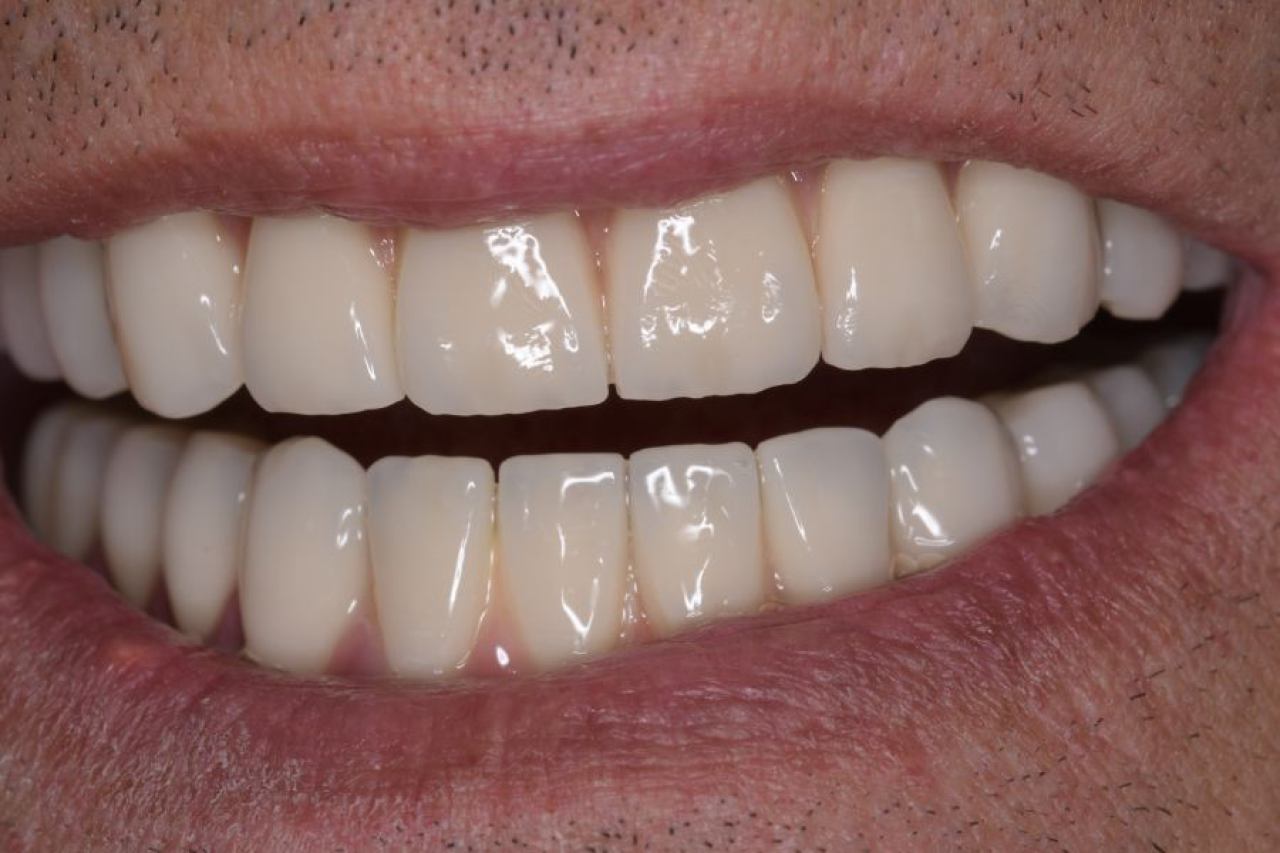

Protetika - mostovi i krunice

Dentalna protetika uključuje fiksne i mobilne radove kojima se nadoknađuje djelomična ili potpuna bezubost. Njihov cilj je povratiti funkciju žvačnog sustava i u konačnici, vrhunsku estetiku.

Marković Dental Clinic u svojoj ponudi ima metalkeramičke radove, potpunokeramičke radove, te u narodu zvane „bezmetalne", odnosno zirkonske radove.

Estetska dentalna medicina

Izbjeljivanje zubi i zubne ljuskice zaštitni su znak Hollywoodskog osmijeha. Izbjeljivanje nije štetno za zube i ne oštećuje caklinu.

Ukoliko niste zadovoljni svojim osmijehom tu je DSD ili Digital Smile Design kojim u okvirima naših mogućnosti ispunjavamo vaše želje „Hollywood smile" ljuskicama, minimalno invanzivnim preparacijama zuba.

Marković Dental Clinic uvijek na prvom mjestu ima zdravlje zubi i zadovoljstvo svakog pacijenta. Koristimo najmoderniji software gdje je pacijentu moguće virtualno prikazati nove zube te kasnije kreirati novi osmijeh protetskim radom, ljuskicama, krunicama ili mostovima.